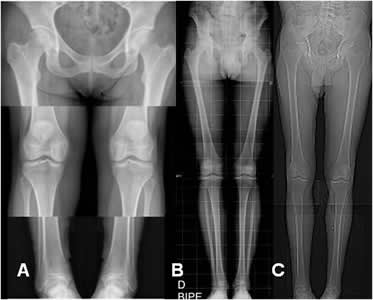

Genu valgo: Angulo femorotibial menor de 173º.

Fig 98 A. Genu valgo de origen femoral.

Eje desplazado lateralmente y líneas tangenciales paralelas.

Fig 98 B. Genu valgo de origen tibial.

Eje desplazado lateralmente y líneas tangenciales con ángulo de vértice lateral.

Genu varo: Angulo femorotibial mayor de 177º.

Fig 98 C. Genu varo de origen femoral.

Eje desplazado medialmente y líneas tangenciales paralelas.

Fig 98 D. Genu varo de origen tibial.

Eje desplazado medialmente y líneas tangenciales con ángulo de vértice medial.

Las dismetrías se pueden calcular, con: (1, 2, 3, 8). (Fig 102).

Los puntos de referencia para hacer la medición son el borde superior de la cabeza femoral, el borde inferior del cóndilo femoral medial, la eminencia intercondílea tibial y el borde inferior de la tibia. (1, 2, 3). (Fig 103).

Las proyecciones permiten determinar la causa, cuantificar las diferencias y siempre deben incluir las crestas iliacas. (2, 3). (Fig 104 A y B y 105).

Fig 102. Longitud de extremidades.

A: Rx simple con 3 disparos en las articulaciones, en una misma película.

B: Telemétrica de miembros inferiores.

C: Escanigrama de TAC.

Fig 103. Longitud de extremidades.

A y B: Rx simple. Medición de las extremidades. En el fémur desde el borde superior de la cabeza femoral, hasta el borde inferior del cóndilo medial y en la pierna desde la eminencia intercondilea, hasta el borde inferior de la tibia.

Fig 104 A. Acortamiento.

Test de Farill. Acortamiento de la extremidad izquierda, a expensas del fémur.

Fig 104 B. Acortamiento.

Rx AP. Acortamiento de la extremidad izquierda, a expensas del fémur por fractura antigua y consolidada del tercio distal.

Fig 105. Acortamiento.

Rx AP. Acortamiento de la extremidad izquierda, sin encontrar lesiones focales y secundario a disminución en la longitud de la tibia.